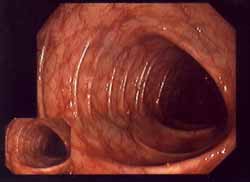

-- gastritis atrófica

(que no es provocada por una producción de ácido

aumentada, pero va provocar una subfunción de ciertas

células de la membrana mucosa)

-- glomerulonefritis

(una clase de nefritis: partes de riñones son atacadas o

van ser depositados complejos inmunológicos)

-- diabetes tipo I

(afectado es la formación de la insulina en las células B

de las "islas Langerhans" en el páncreas)

-- enfermedades

inflamatorias intestinales como colitis ulcerosa

(afectados son partes de la pared intestinal) y enfermedad

de Crohn (afectadas son fibras reticlinas de la pared

intestinal) (eso fue descrito la primera vez en los años

1920s)